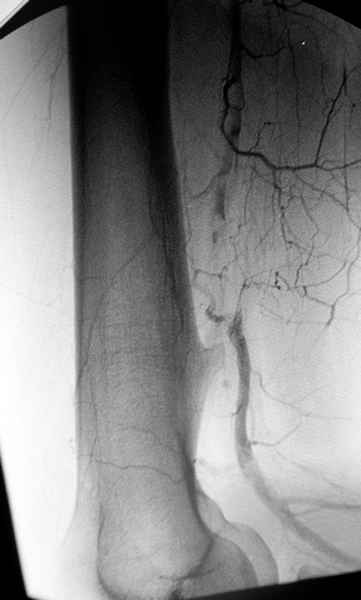

áÎÇÉÏÇÒÁÆÉÑ ÐÏÄÔ×ÅÒÄÉÌÁ ×ÁÓËÕÌÑÒÎÕÀ ÁÎÅ×ÒÉÚÍÕ × ÒÅÚÕÌØÔÁÔÅ ÄÁ×ÌÅÎÉÑ

ÜËÚÏÓÔÏÚÏÍ. óÏ×ÍÅÓÔÎÏ Ó ÓÏÓÕÄÉÓÔÙÍ ÈÉÒÕÒÇÏÍ ÂÙÌÁ ÐÒÏ×ÅÄÅÎÁ

ÐÌÏÓËÏÓÔÎÁÑ ÒÅÚÅËÃÉÑ Ó ÄÁÌØÎÅÊÝÉÍ ×ÏÓÓÔÁÎÏ×ÌÅÎÉÅÍ ÓÏÓÕÄÁ ×ÅÎÏÚÎÙÍ

ÇÒÁÆÔÏÍ.

éÍÑ     : #1 angiogram 2.jpg

ôÉÐ     : image/jpeg

òÁÚÍÅÒ  : 25405 ÂÁÊÔÏ×

ïÐÉÓÁÎÉÅ: ÏÔÓÕÔÓÔ×ÕÅÔ

Url     : http://weborto.net:8080/pipermail/ortho/attachments/20080403/4b5e6a95/attachment-0005.jpg